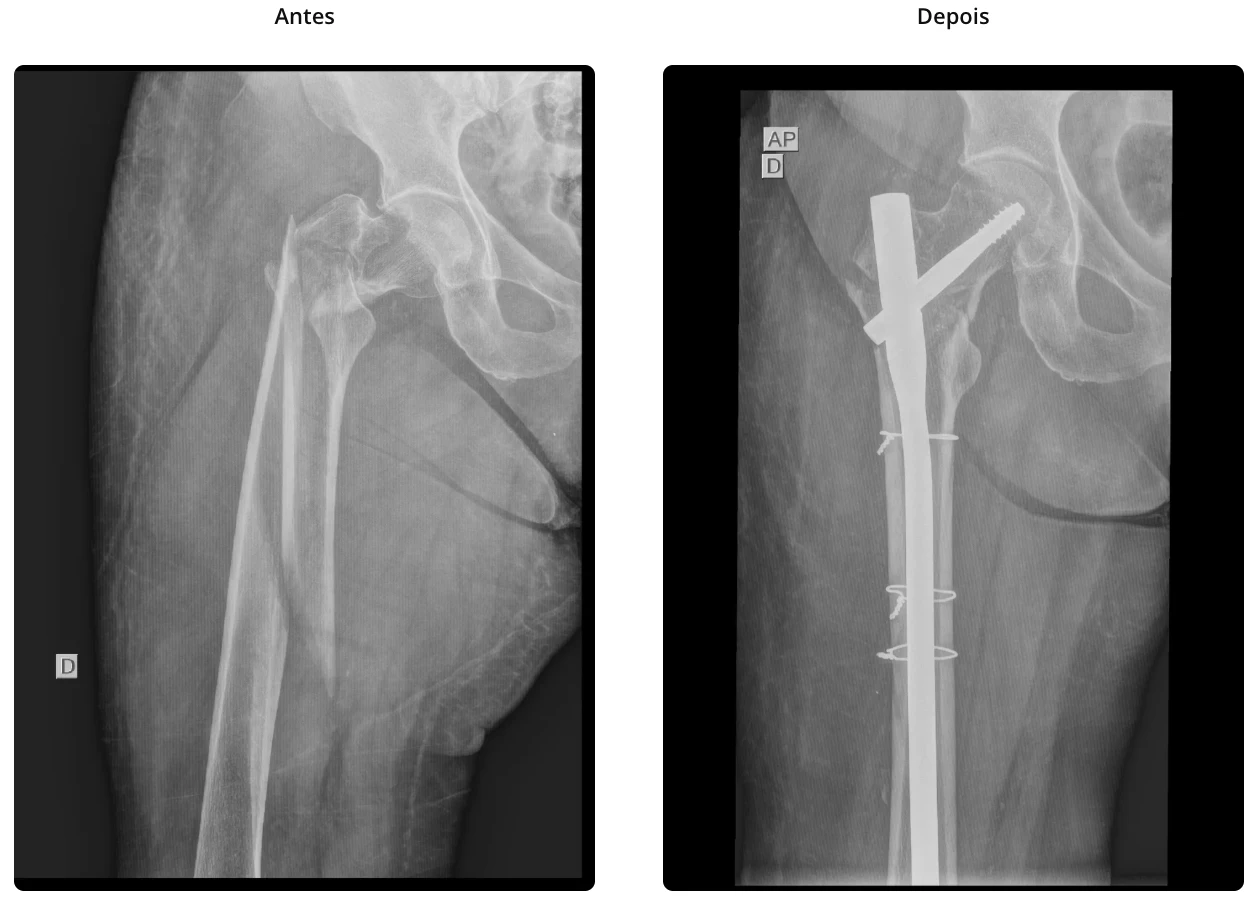

As fraturas de acetábulo são lesões complexas que afetam a articulação do quadril na região do osso pélvico. Essas fraturas ocorrem devido a traumas de alta energia como acidentes automobilísticos ou quedas de altura. Geralmente necessitam uma abordagem completa do politrauma e invariavelmente cursam com internação hospital até a sua resolução.

O tratamento em alguns casos pode ser conservador, utilizando imobilização no leito e restrição de carga ou tratamento cirúrgico dependendo da complexidade da lesão e idade do paciente. A cirurgia pode envolver a fixação da fratura com placas e parafusos, visando restaurar a anatomia do quadril e permitir a recuperação funcional. Um acompanhamento adequado e a reabilitação são fundamentais para garantir a recuperação e a volta às atividades diárias, minimizando o risco de complicações futuras como principalmente a artrose pós traumática.